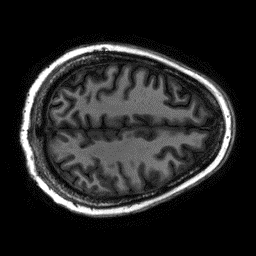

Reconstructing magnetic resonance (MR) images from undersampled data is a challenging problem due to various artifacts introduced by the under-sampling operation. Recent deep learning-based methods for MR image reconstruction usually leverage a generic auto-encoder architecture which captures low-level features at the initial layers and high?level features at the deeper layers. Such networks focus much on global features which may not be optimal to reconstruct the fully-sampled image. In this paper, we propose an Over-and-Under Complete Convolu?tional Recurrent Neural Network (OUCR), which consists of an overcomplete and an undercomplete Convolutional Recurrent Neural Network(CRNN). The overcomplete branch gives special attention in learning local structures by restraining the receptive field of the network. Combining it with the undercomplete branch leads to a network which focuses more on low-level features without losing out on the global structures. Extensive experiments on two datasets demonstrate that the proposed method achieves significant improvements over the compressed sensing and popular deep learning-based methods with less number of trainable parameters. Our code is available at https://github.com/guopengf/OUCR.